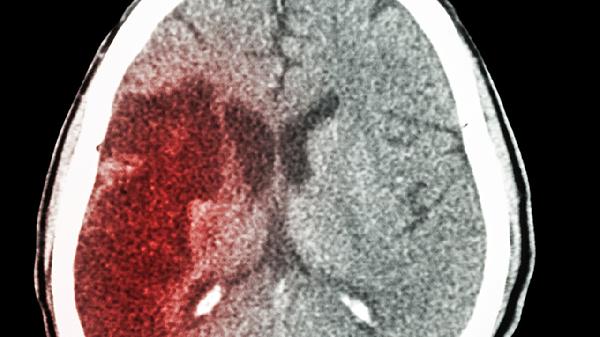

醒脑降压丸适合用于原发性高血压的辅助治疗,尤其是伴有头痛眩晕、面红耳赤、易怒等肝阳上亢表现的患者。药物中的活性成分能够帮助扩张外周血管,降低血管阻力,同时调节中枢神经系统功能,达到降压效果。长期服用可在一定程度上预防高血压引发的脑血管并发症。